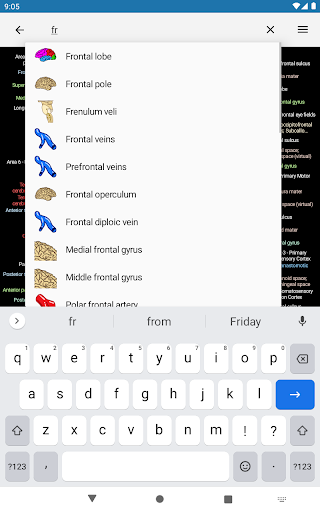

- Mudah menemukan struktur anatomi berkat pencarian indeks

*Temukan bagian anatomi Anda dengan lebih mudah berkat fitur pencarian baru yang lebih intuitif dan canggih